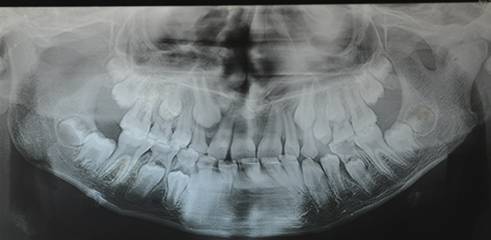

TMJ ANKYLOSIS SURGICAL MANAGEMENT, GAP ARTHROPLASTY WITH TMF FLAP